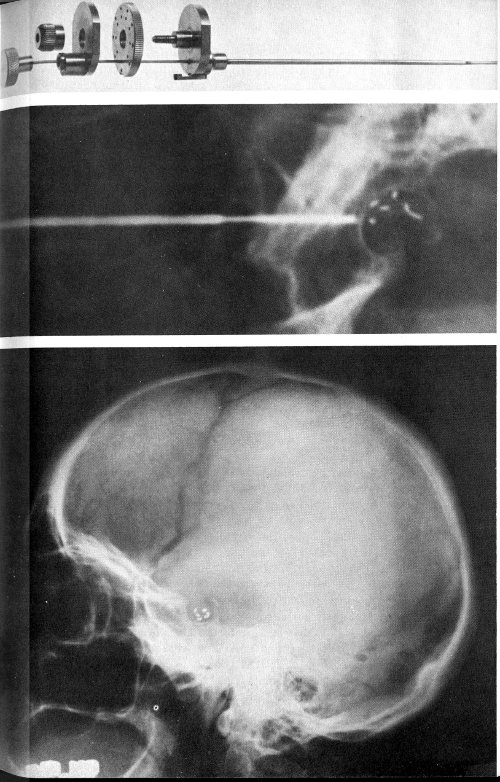

The needle used for implantation of yttrium-90 pellets into the pituitary gland is shown in the top photograph. In the center X ray the needle is in place and the pellets have just been passed through it into the bone area surrounding the pituitary gland. The bottom X ray shows the needle withdrawn and the pellets within the bone.